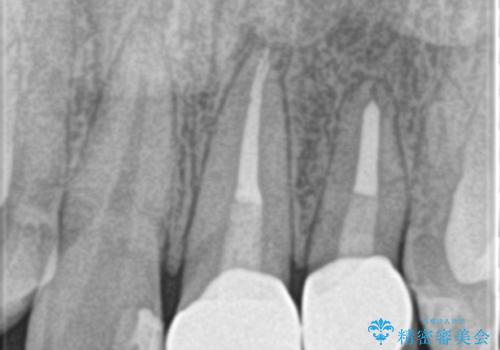

レントゲンを撮影すると、不適合のかぶせ物が装着されており、根管治療も不十分でした。

左上の1番目、2番目の歯を根管治療からの再治療を行う計画としました。

レントゲン上でも適合の良いかぶせ物が装着できています。